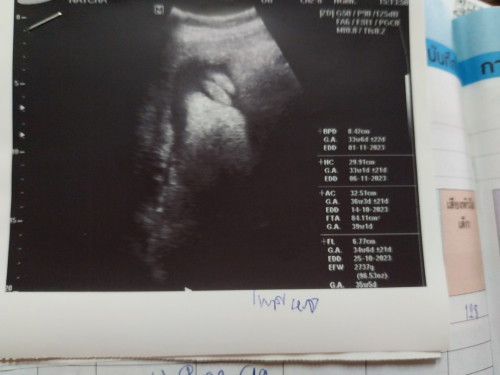

ผลอัลตราซาวด์แบบนี้ชัวร์เพศ100%ไหมคะ

แบบนี้เพศ หญิง.ชัวร์100%ไหมคะ สอบถามแม่ๆน้า ไม่ดราม่านะคะ#ขอบคุณล่วงหน้านะคะ

อายุครรภ์เยอะจะดูยากหน่อยค่ะแม่ ดูไม่ออกเลยว่ามันเป็นส่วนไหน

เป็นกลีบเลยค่ะ ไม่น่าจะมีโอกาสเป็นชายนะคะ

กลีบเยอะชัดเเจ๋วเลยคะผู้หญิง

มาเปนกลีบเลยค่ะผู้ ญ100%

ผู้หญิงค่ะ